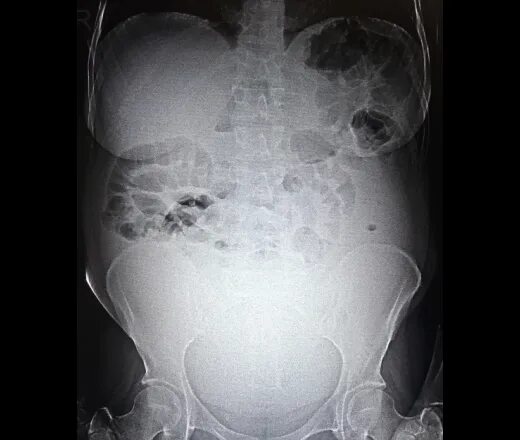

3 обп